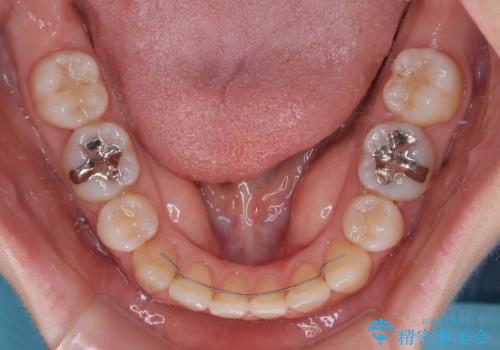

舌の突出癖が非常に強く、その影響で隙間ができてしまったので、舌のトレーニングをしっかりと行っていただきました。

上顎歯列は歯の移動量が少なかったため、セラミッククラウンは装置を装着せずに治療を終えることができました。